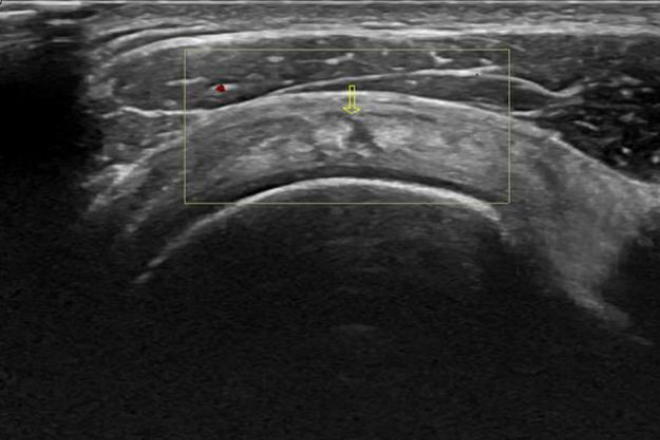

EXLORACIÓN ULTRASONOGRÁFICA DEL HOMBRO:

Debe existir correlación clínica para la realización de este estudio, se pueden obtener con esto datos importantes que complementen el diagnostico, es importante realizar imágenes duales de las estructuras a estudiar para realizar así un comparativo y además en posición estática y móvil.

En conclusión: de primera instancia será difícil identificar las estructuras por lo que se debe practicar lo mas que se pueda para poder distinguir las inserciones de los músculos, poder diferenciar los tendones y las alteraciones que se pueden presentar en un musculo o en un grupo de músculos.